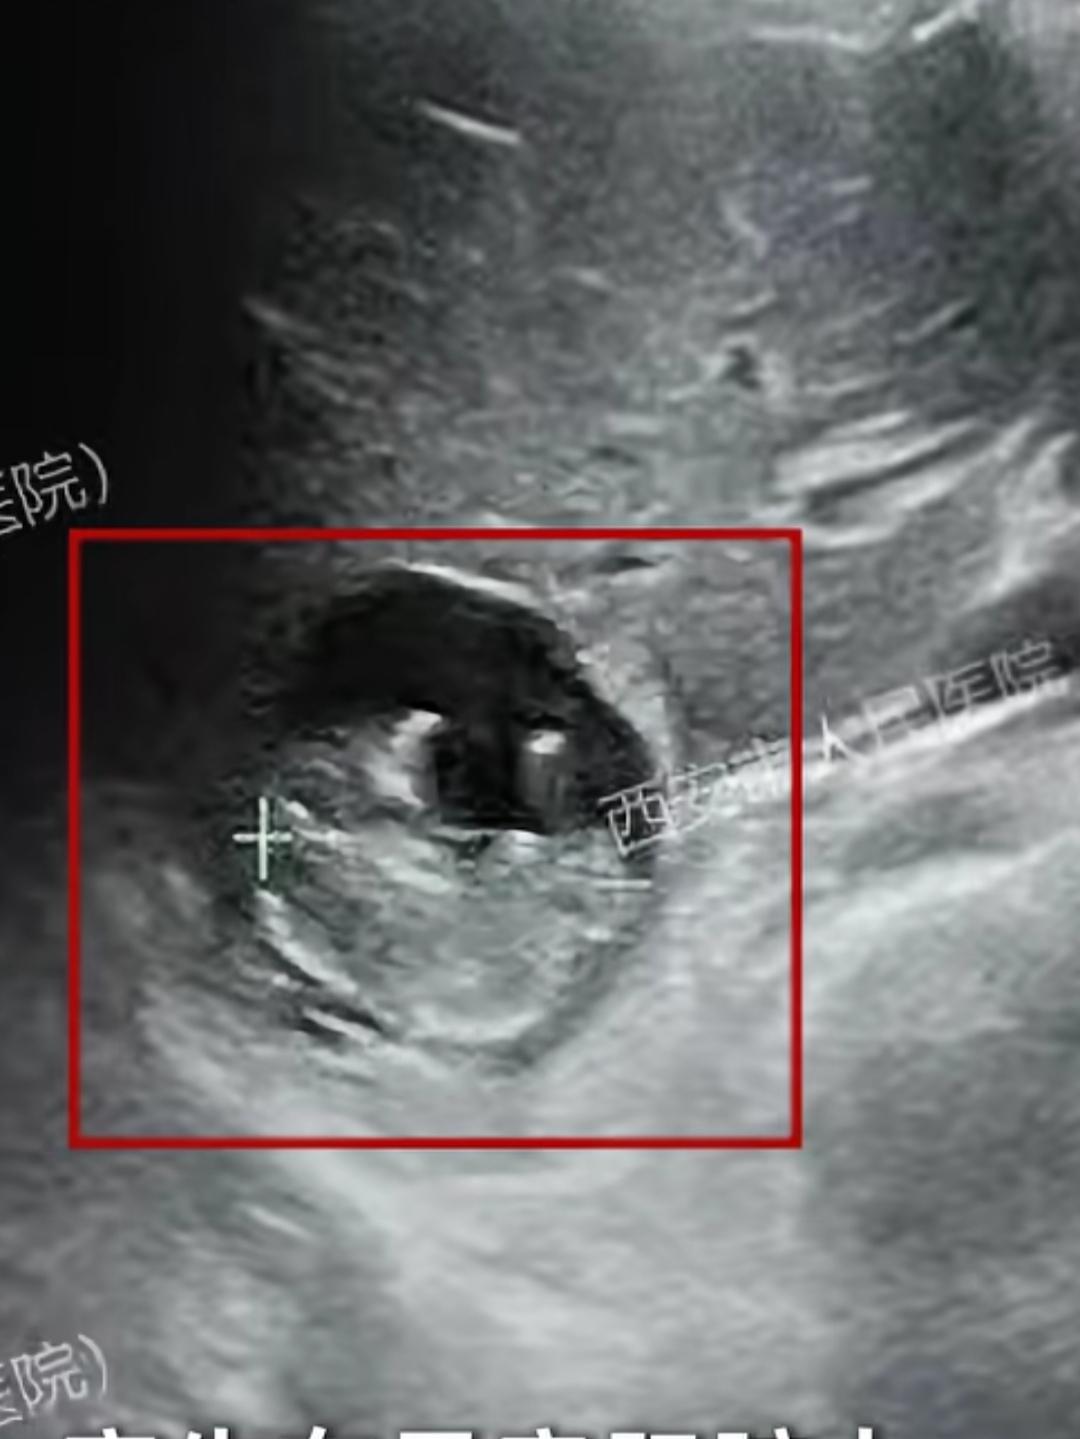

一位满怀期待迎接新生命的孕妈,竟然在胎死宫内整整6周后才后知后觉,这位女士和丈夫备孕了很久,终于成功怀孕,全家人都沉浸在即将迎来新生命的喜悦里,在怀孕初期,她其实有过一些身体上的小变化,比如肚子偶尔隐隐作痛,原本明显的孕吐反应也慢慢消失了。但因为她觉得怀孕后身体不舒服是正常的,加上怕麻烦、觉得去医院检查费钱,就一直心存侥幸,没有及时去医院做正规的产检。就这样过了一个多月,她的肚子不仅没像其他孕妈那样变大,反而出现了不规则的阴道出血,这时候她才慌了神,急忙赶到医院,可医生做完B超后,给出的结果如同晴天霹雳,宝宝早已没有胎心,在肚子里停止发育已经整整6周了,因为拖延的时间太久,死亡的胚胎长期滞留在宫腔内,她不仅要承受失去孩子的巨大心理创伤,还要面临清宫手术,身体也面临着宫腔感染等风险。这种情况在医学上被称为“稽留流产”,也就是我们常说的“过期流产”,简单来说,就是胚胎或胎儿已经死亡,却没能及时自然排出,滞留在了子宫腔内,很多孕妈都有一个误区,觉得流产一定会有剧烈的腹痛、大出血,但稽留流产恰恰相反,它非常隐蔽,患者可能只是早孕反应(如孕吐、嗜睡)突然消失,或者只有少量的褐色分泌物,甚至像这位女士一样,前期没有任何明显征兆。为什么胎儿停止发育了,妈妈的身体却没有立刻发出警报呢?这主要是因为胎盘还在工作,即便胎儿已经死亡,胎盘在一段时间内依然保持着活性,继续分泌孕激素(HCG),让妈妈的身体误以为怀孕还在正常进行,所以孕吐、胸胀等妊娠反应可能依然存在,这就导致死胎很难被及时察觉。孕期再忙、再怕麻烦,也千万不能忽视按时产检,身体发出的任何异常信号,比如孕吐突然消失、腹部隐痛、阴道出血等,都不是小事,一旦发现不对劲,一定要第一时间就医。怀孕从来不是一个人的事,家人的关心和及时的医疗检查,才是对宝宝生命最大的负责。热点事件来源:纵览新闻